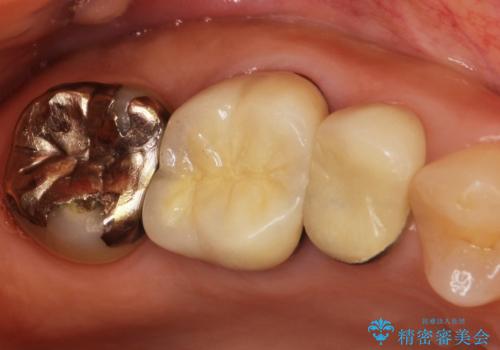

- 右上の奥歯がしみるとのことで確認すると、右上の一番奥の歯の銀歯の下が虫歯になっていました。

かなり大きな銀歯が装着されていたので、かぶせ物にて治療を行うこととなりました。

同時に右上の後ろから3番目の歯のかぶせ物も適合が悪かったので同時に治療することとなりました。